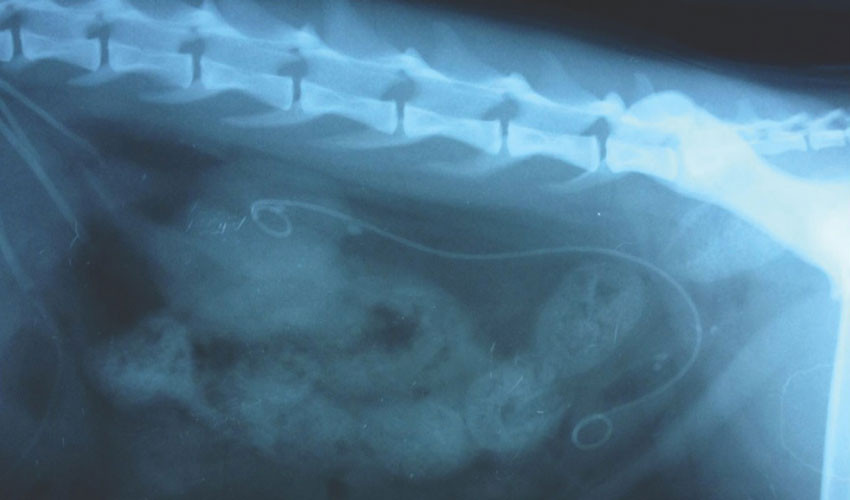

Для стентирования мочеточников почки используют стенты длиной от 6 до 80 см. Они могут быть изготовлены из разных материалов: полиуретана, силикона, С-flex, с покрытием гидрогелем. Чаще всего используют двухпетлевые стенты (J-J стент) — у них оба кончика закручены в виде «поросячьих хвостиков». Существуют однопетлевые модели. У некоторых в определенных местах есть утолщения.

Трансуретральное стентирование мочеточника обычно продолжается 25–30 минут. Врач вводит в мочевой пузырь эндоскопический инструмент — цистоскоп, — заполняет орган жидкостью для лучшего обзора, осматривает слизистую оболочку, находит устье мочеточника и заводит в него стент. Для того чтобы понять, на какую глубину введен стент, на нем нанесены специальные деления. Когда он полностью введен, цистоскоп удаляют, из мочевого пузыря выводят жидкость. Процедура завершена.

При чрескожном пункционном стентировании мочеточника стент вводят через прокол на коже, сначала в почечную лоханку, затем заводят через мочевой пузырь в мочеточник. Вмешательство проводят под контролем рентгена. Зачастую операцию выполняют в два этапа. Сначала выполняют нефростомию: создают отверстие на коже, которое ведет в почечную лоханку, и устанавливают в него трубку для оттока мочи. Через 5–7 дней через это отверстие выполняют стентирование.